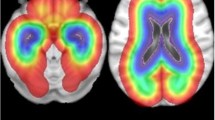

Heatmap of tumor showing distribution of the three molecular groups: oligodendrogliomas (IDH mutated, 1p19q co-deleted) in left panels (n = 50), astrocytomas (IDH mutated, 1p19q non-co-deleted) in middle panels (n = 64) and astrocytomas (IDH wild-type) in right panels (n = 45). Increasing intensity of color corresponds to increasing number of overlapping tumors within the same group. Numbers on left corresponds to z-coordinates in the MNI space and sections marked 0 and -20 represents upper and lower part of hippocampus, respectively